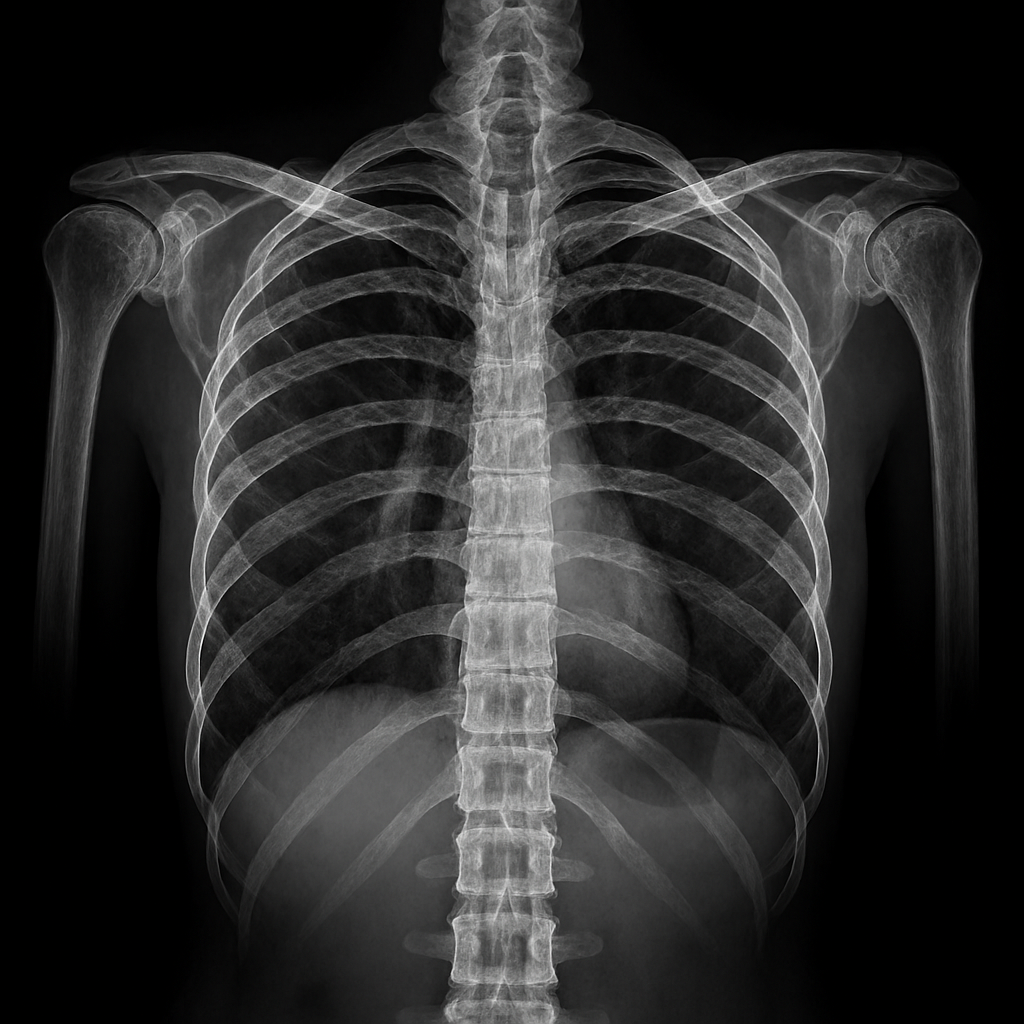

The Role of Elite Medical Support

Professional athletes have access to multidisciplinary medical teams that optimize every phase of recovery. Sports physicians, physiotherapists, orthopedic surgeons, and nutritionists collaborate to create individualized treatment plans. Diagnostic imaging such as MRI and ultrasound allows precise identification of tissue damage – guiding targeted interventions. Surgical techniques are often minimally invasive – reducing recovery time and preserving function. Rehabilitation protocols are progressive and evidence-based – incorporating strength, mobility, proprioception, and sport-specific drills. Manual therapy, dry needling, and neuromuscular re-education accelerate tissue remodeling. Nutrition is tailored to support healing – with emphasis on protein synthesis, anti-inflammatory compounds, and micronutrient balance. Recovery is monitored through biomarkers, performance metrics, and subjective feedback. This level of care is rarely available to the general public – creating a disparity in recovery outcomes.